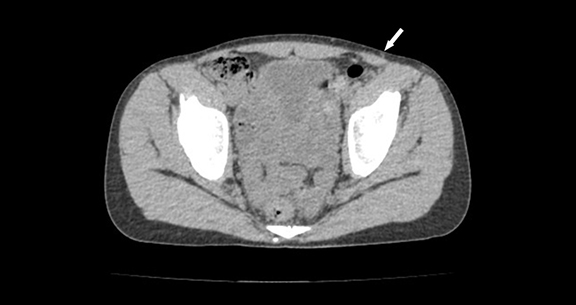

【症例5】 30代男性

2年前にコロナ罹患したのち腹痛が増悪。電撃痛も出現し当院を受診。

CTで腹直筋の菲薄化と変性が疑われ、疼痛部位に一致して皮神経が強く描出された。手術を施行し皮神経を切除。皮神経に隣接して血管が交差していた。電撃痛は消失。病理所見では皮神経の広範な変性を認めた。